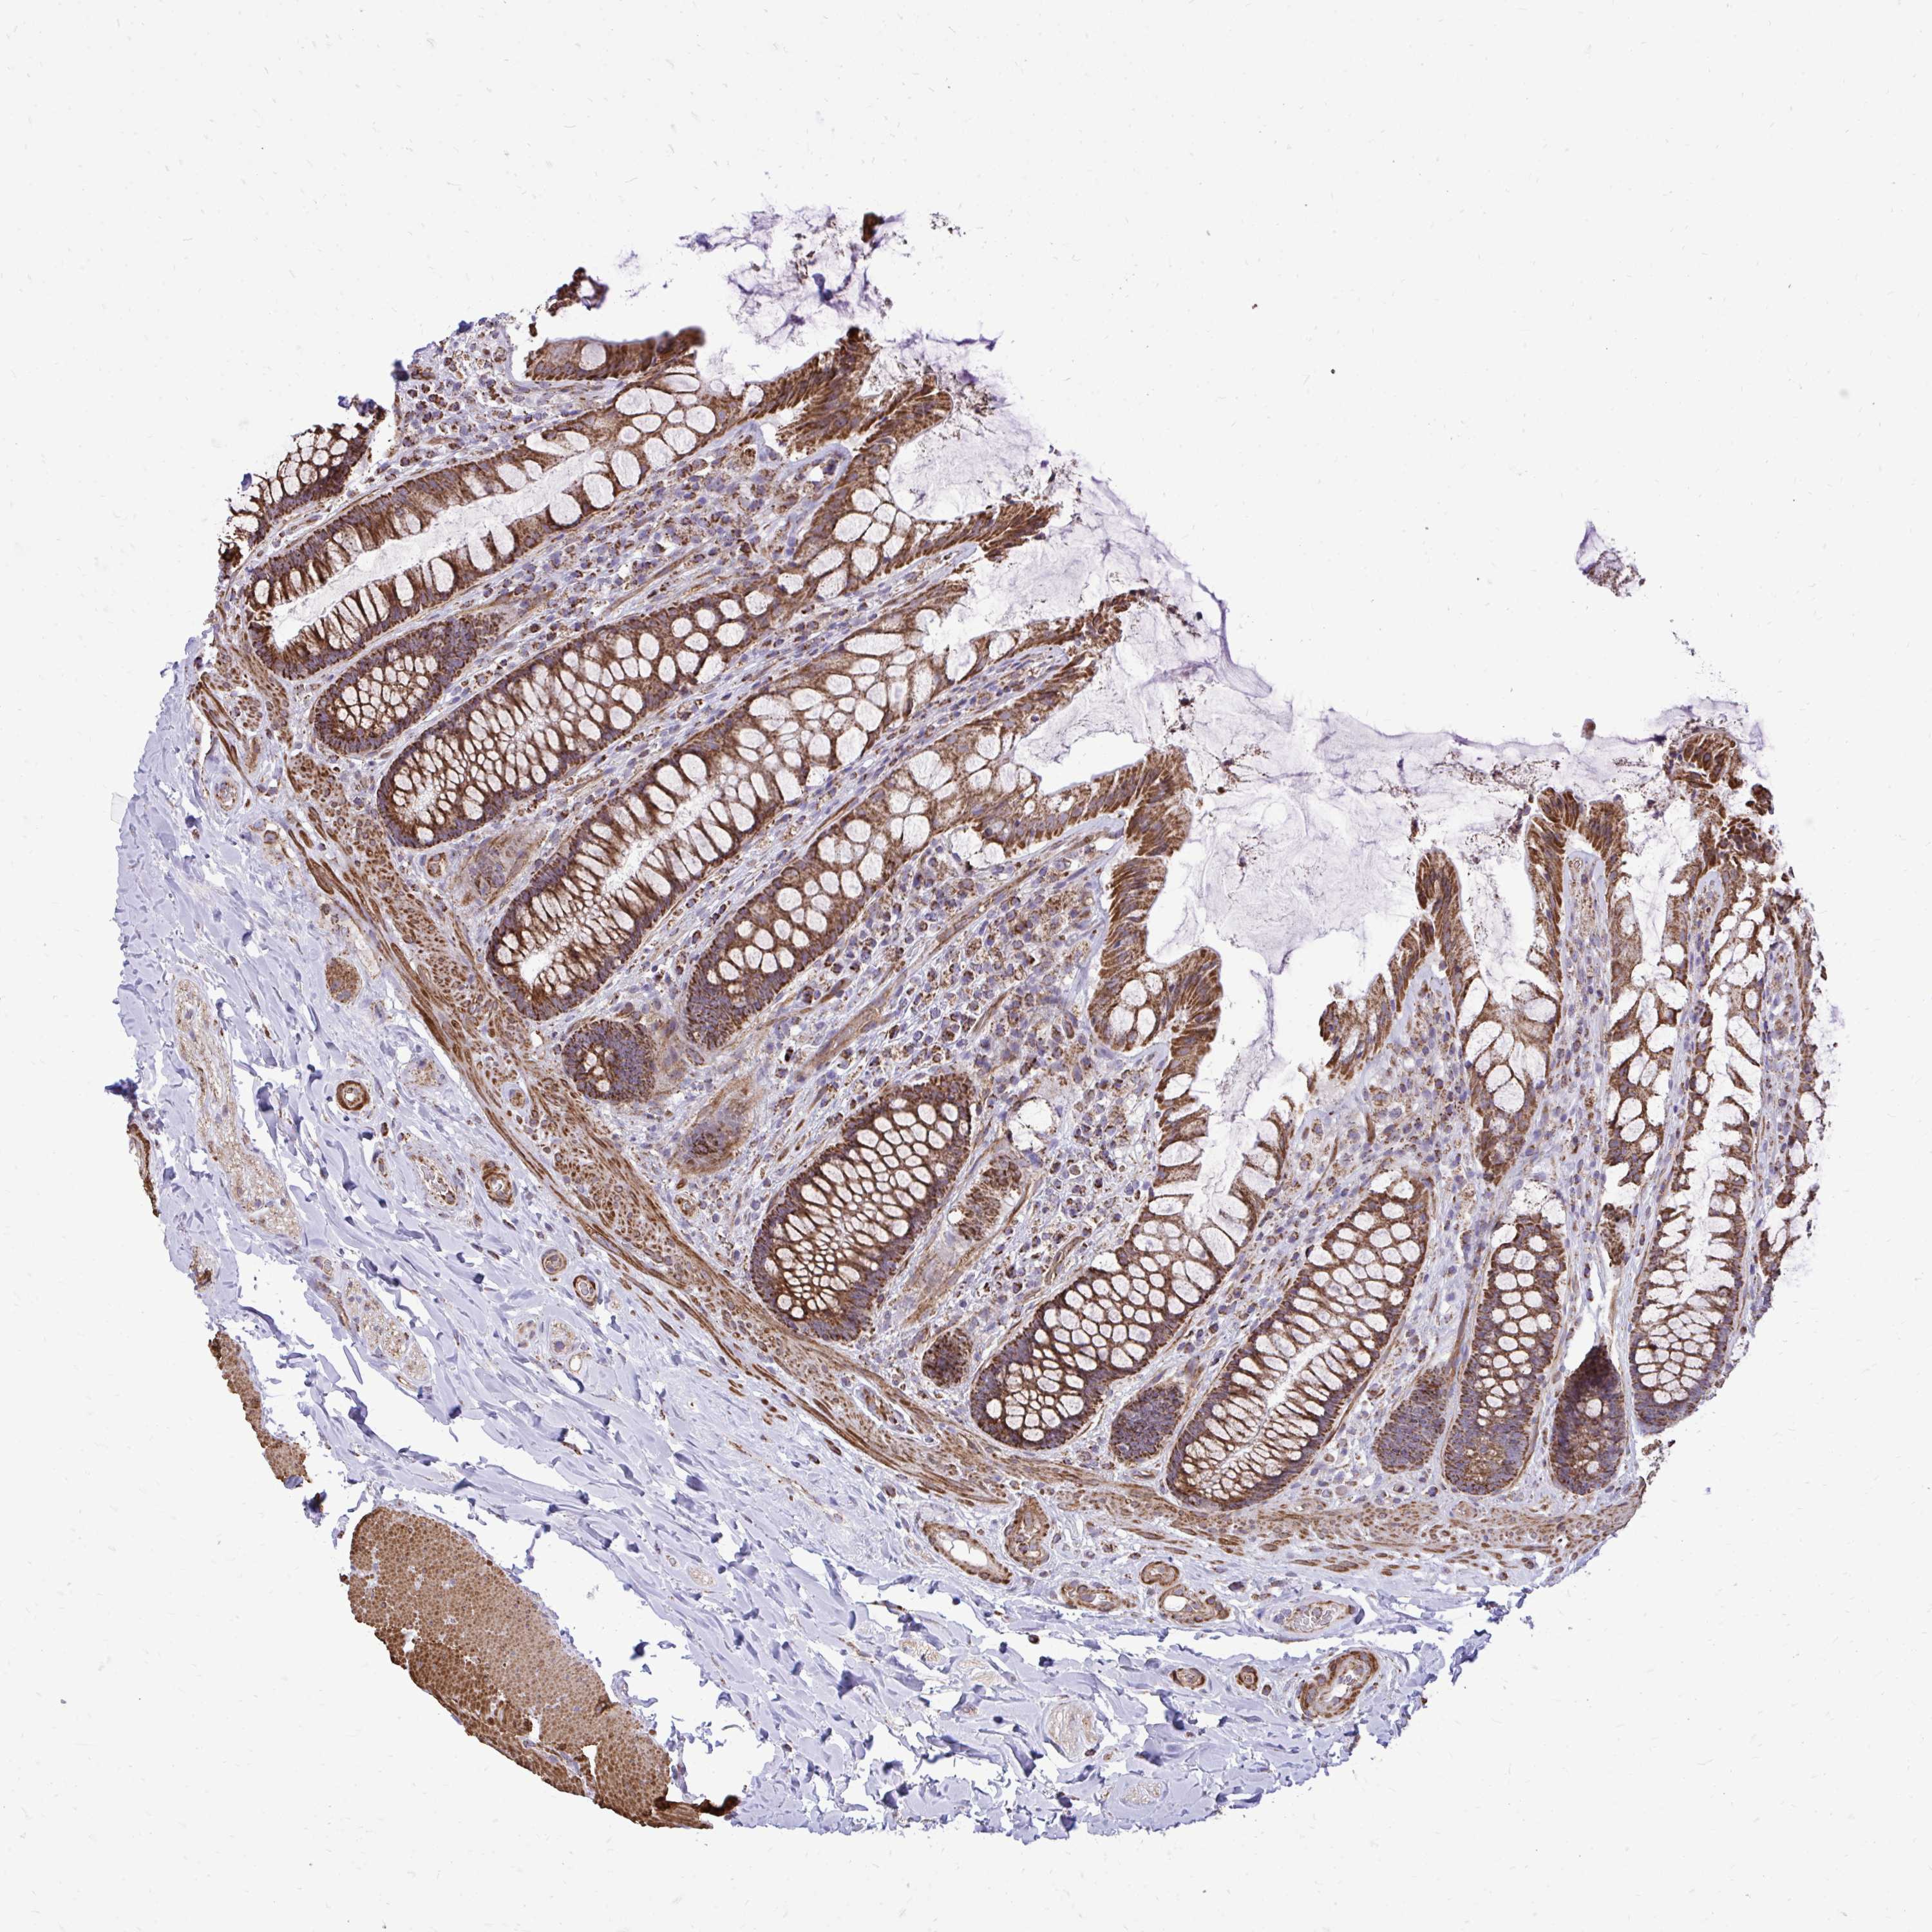

UBE2C